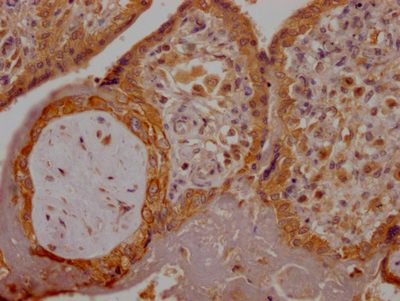

IHC image of CSB-RA280380A0HU diluted at 1:100 and staining in paraffin-embedded human colon cancer performed on a Leica BondTM system. After dewaxing and hydration, antigen retrieval was mediated by high pressure in a citrate buffer (pH 6.0). Section was blocked with 10% normal goat serum 30min at RT. Then primary antibody (1% BSA) was incubated at 4℃ overnight. The primary is detected by a Goat anti-rabbit IgG polymer labeled by HRP and visualized using 0.05% DAB.

IHC image of CSB-RA280380A0HU diluted at 1:100 and staining in paraffin-embedded human placenta tissue performed on a Leica BondTM system. After dewaxing and hydration, antigen retrieval was mediated by high pressure in a citrate buffer (pH 6.0). Section was blocked with 10% normal goat serum 30min at RT. Then primary antibody (1% BSA) was incubated at 4℃ overnight. The primary is detected by a Goat anti-rabbit IgG polymer labeled by HRP and visualized using 0.05% DAB.